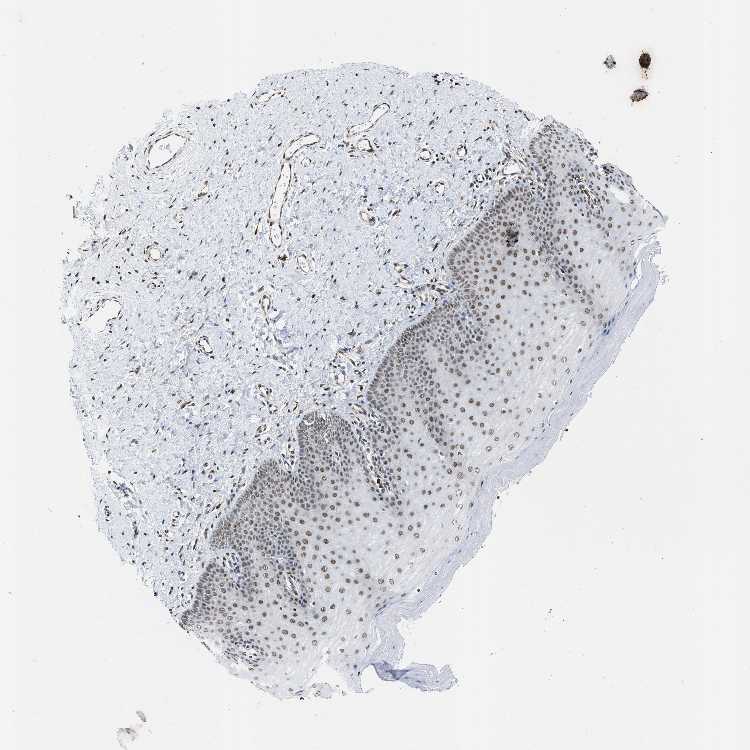

TISSUE PRIMARY DATA CERVIX Show tissue menu

CERVIX - Antibody stainingi

Antibody staining in the annotated cell types in the current human tissue is reported as not detected, low, medium, or high, based on conventional immunohistochemistry profiling in selected tissues. This score is based on the combination of the staining intensity and fraction of stained cells.

Each image is clickable and will lead to virtual microscopy that enables deeper exploration of all samples and also displays staining intensity scores, fraction scores and subcellular localization as well as patient and tissue information for each sample.

Antibody HPA016832Antibody HPA020076Antibody CAB001969

Glandular cells -MediumHigh

Squamous epithelial cells MediumMediumHigh